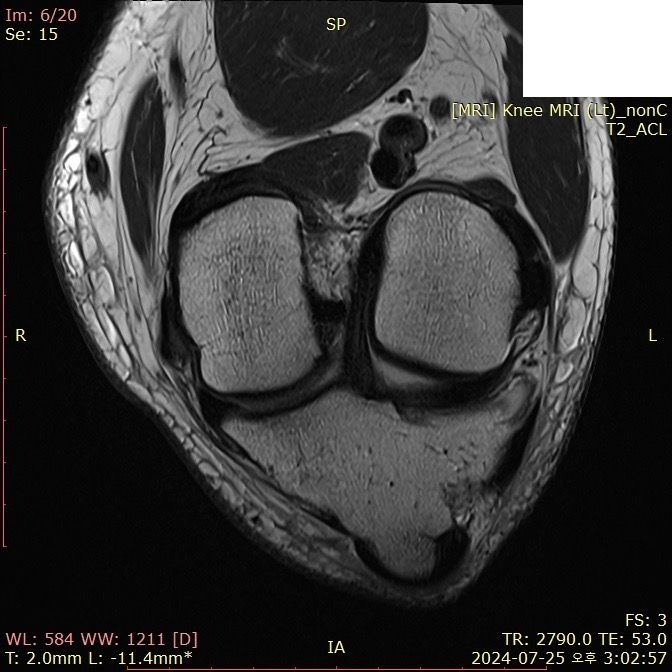

무릎 ACL(전방십자인대) 확인 부탁드려요

아스팔트에 무릎을 부딪쳐 심하게 부어서 mri 찍어봤는데 슬개골 비변위성 골절 판독 받은 건 기억 나는데, 인대는 기억이 잘 안나서 여쭤 봅니다..

전방십자인대 괜찮은가요...??ㅠㅠ

Mri에서 슬개골 비변위성 골절이 판독되었다면 일반적으로 전방십자인대에 대한 언급이 없다면 괜찮을 가능성이 큽니다. 하지만 정확한 진단은 의사와 상담을 통해 확인하는 것이 중요합니다.

전방십자인대 손상이 의심되면 추가적인 검사나 치료가 필요할 수 있습니다!